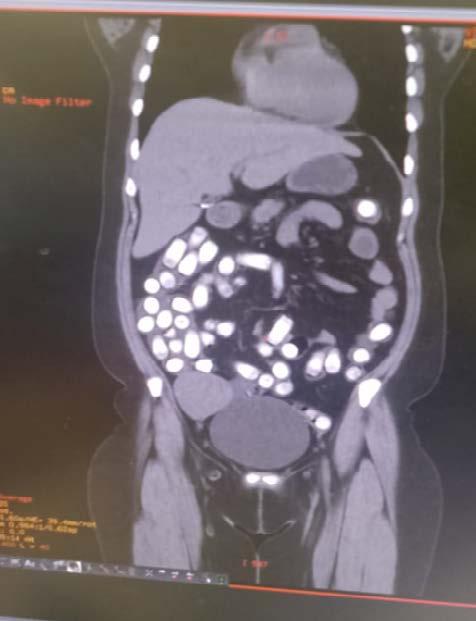

En una operación antidrogas realizada en el Aeropuerto Internacional Jorge Chávez, ubicado en el Callao, efectivos del Departamento Antidrogas detuvieron a dos mujeres que intentaban transportar drogas en la modalidad de “ingesta”.

Las detenidas, identificadas como Nadia Mercedes Vidal Vidal, de 36 años, y Rut Ana Huane Morales, de 28 años, mostraron un evidente nerviosismo mientras esperaban su vuelo con destino a Santiago de Chile en la zona de pago del TUUA (molinete) de salidas internacionales.

Los agentes, tras notar la actitud sospechosa de ambas mujeres, procedieron a realizar un examen de rayos X con el sistema Body Scam, el cual reveló la presencia de “presuntos cuerpos extraños en la cavidad abdominal” de las detenidas.

Ante estos hallazgos, fueron trasladadas de inmediato al hospital Daniel A. Carrión, en Bellavista, para realizarles una tomografía, la cual confirmó la existencia

eIntentaban viajar a Chile con las sustancias dentro de su cavidad abdominal

de objetos extraños en sus cavidades abdominales.

Con conocimiento del representante del Minis -

terio Público, las mujeres fueron puestas bajo custodia policial y permanecen en observación en el área

de Emergencia del nosocomio.

Además de la droga, se les incautaron dos celula-

res, 1700 euros, 2 dólares y 50 soles, que ahora forman parte de la investigación en curso.